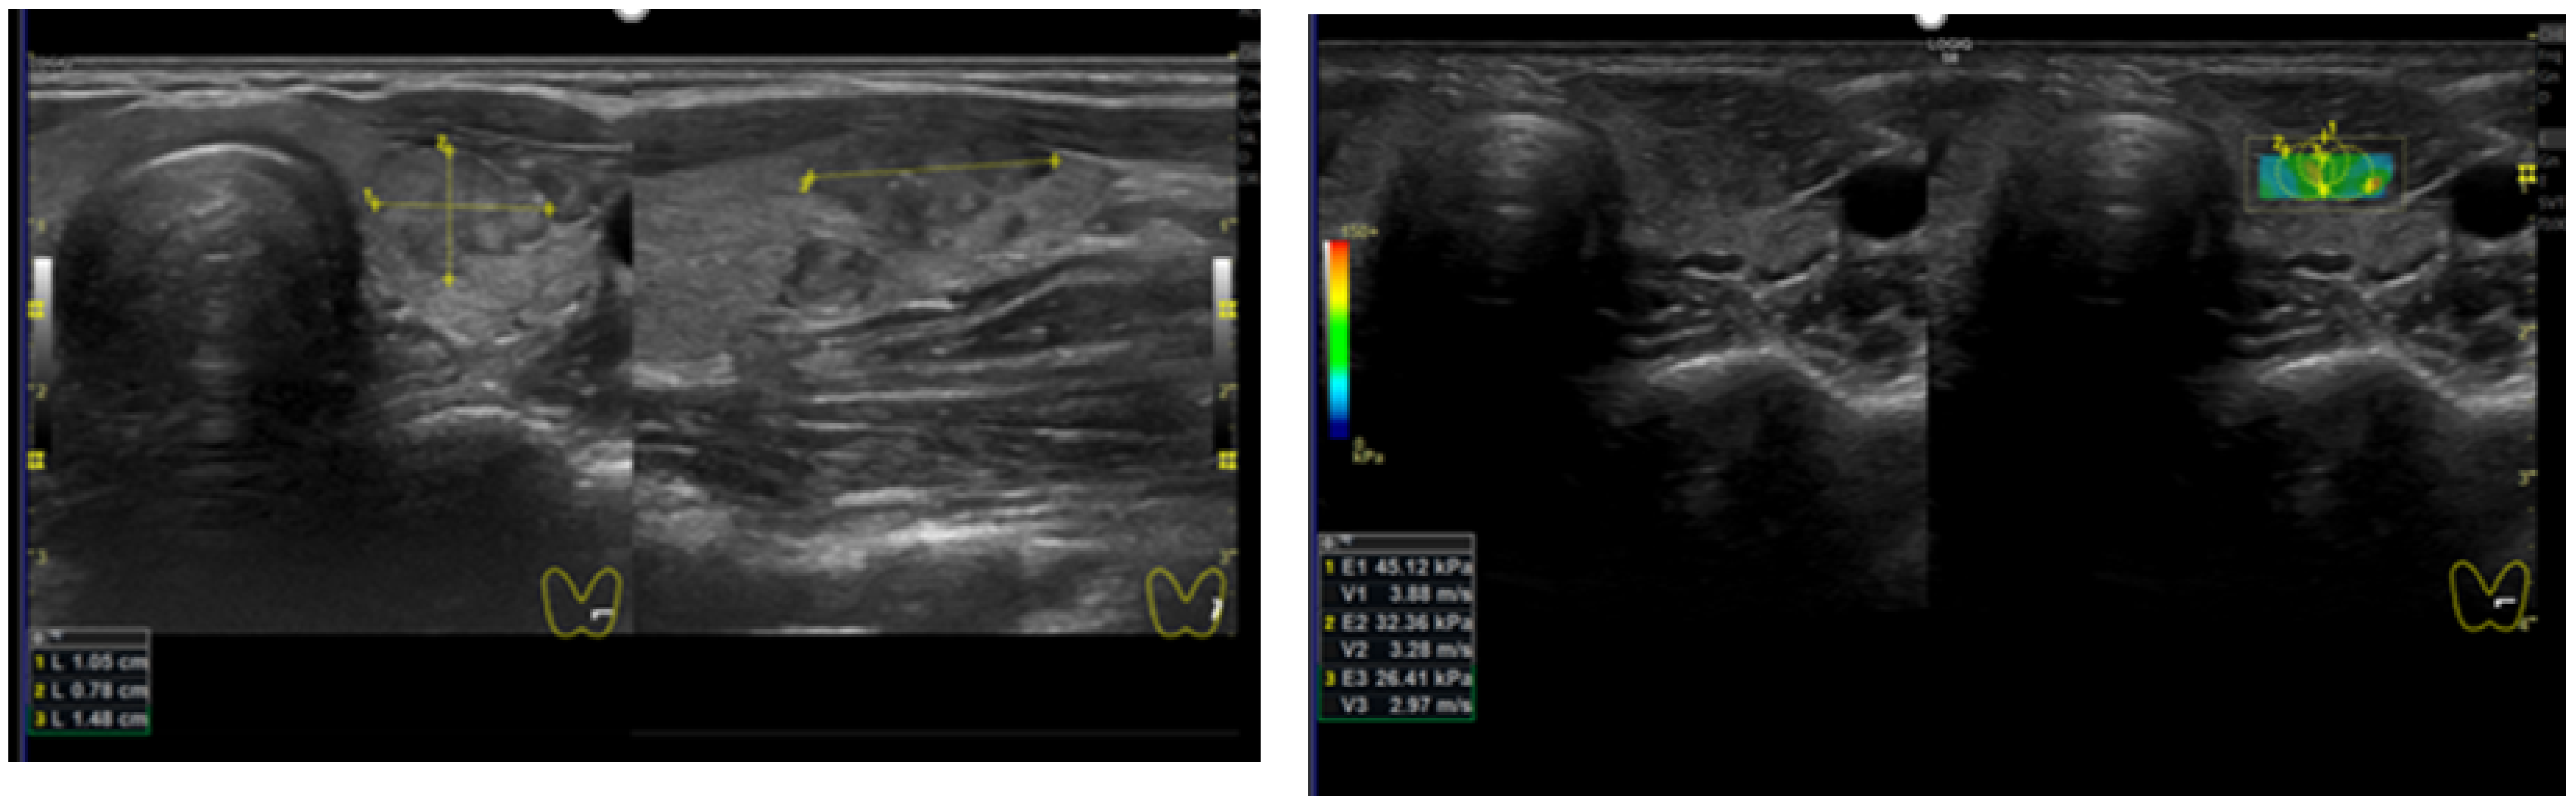

2.2. Thyroid US and SWE